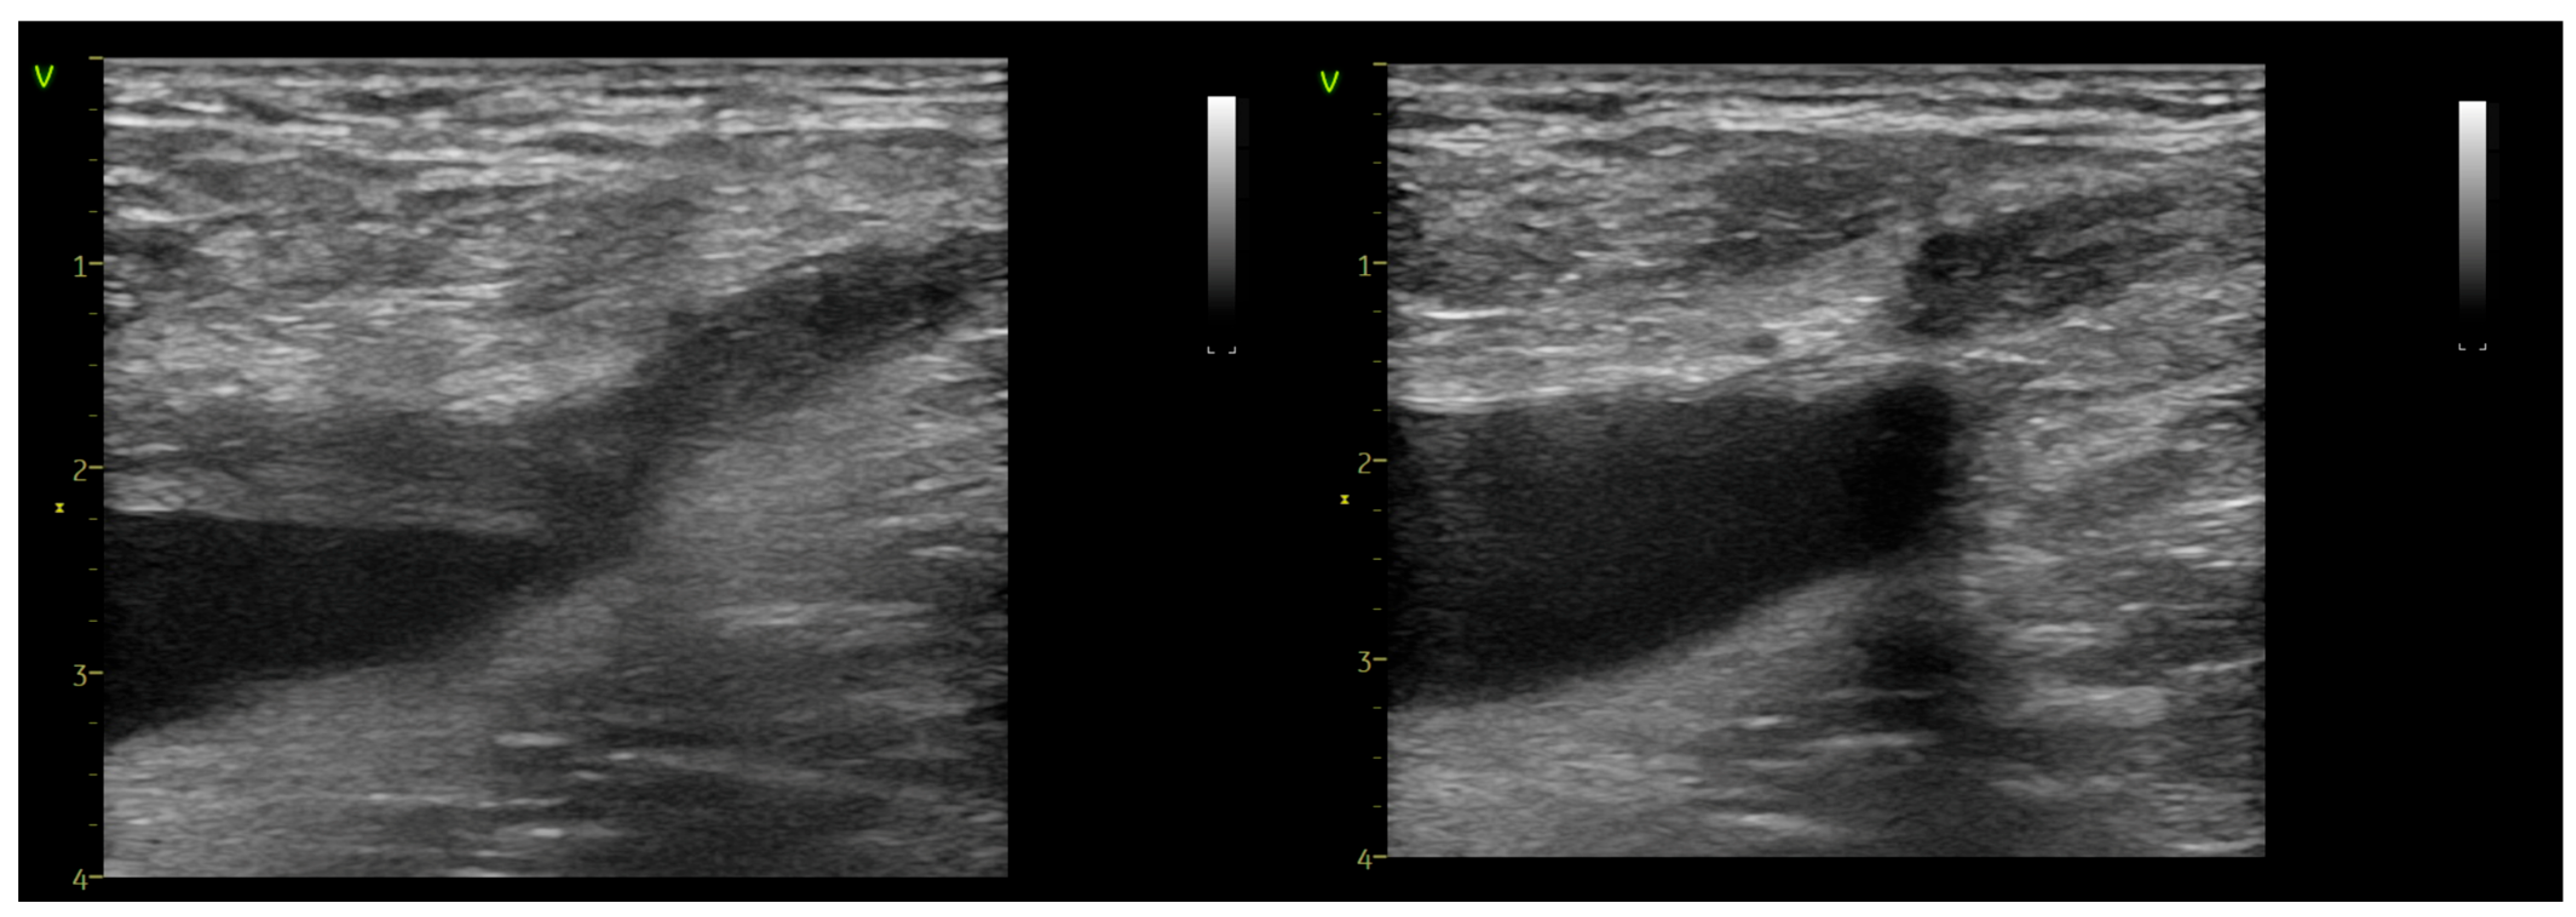

2. Materials and Methods

3. Results